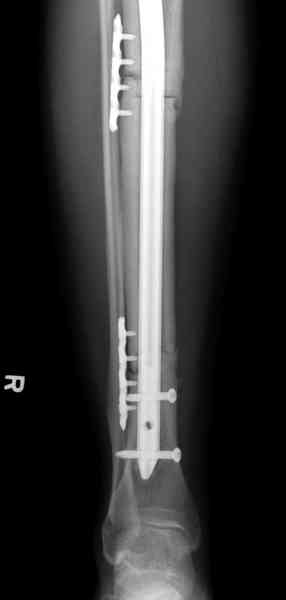

Недавно на нашей ежемесячной Morbidity&Mortality conference мы

разбирали похожий случай, ложный сустав большеберцовой кости после

резекции опухоли.

Оперирован в военном госпитале с заменой сегмента аллокостью

большеберцовой кости и после демобилизации явился для постоянного

наблюдения по месту жительства.

Наши имели проблему со сращением, пришлось им сделать динамизацию,

дополнительную аутопластику.

Имя     : 4 adamantioma ap.jpg